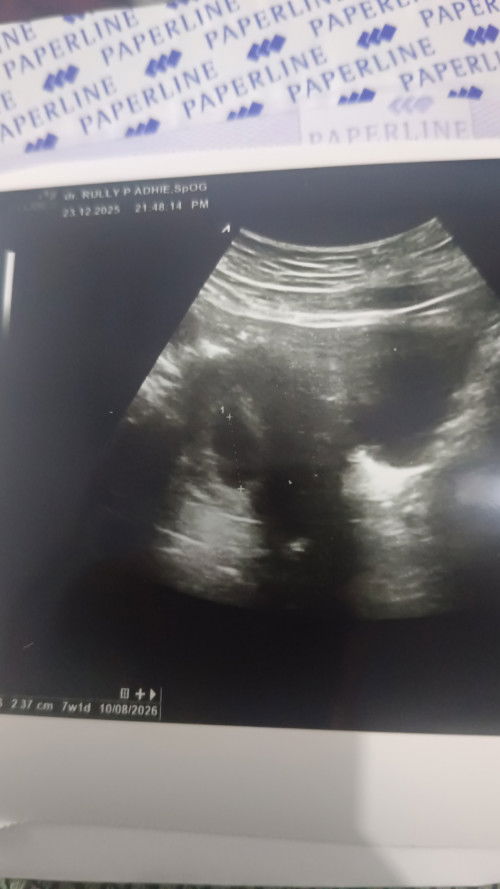

Saya kmrin USG, kalau sesuai HPHT seharusnya 9 minggu. Tapi hasil usg 7 minggu dan sudah ada yolk Salk tapi janin belum terlihat. Disuruh usg 2 minggu lagi, sdh diresep microgest 200 mg tpi masih flek (sdh 2 kali minum - minum nya 2 kali sehari karena flek coklat). Apakah ada bunda bunda seperti saya akhirnya pas usg ada janin berkembang dengan baik, saya dari kmrin sdh nangis bunda. Kuatir, meskipun ini anak ke 4, setelah keguguran 2 kali, anak ketiga 21 bulan. Tapi masih worry #mohonbantujawabbunda #Sharingdong_Bund #bantujawab #sharing #askmommies #sharing

Saya kmrin USG, kalau sesuai HPHT seharusnya 9 minggu. Tapi hasil usg 7 minggu dan sudah ada yolk Salk tapi janin belum terlihat. Disuruh usg 2 minggu lagi, sdh diresep microgest 200 mg tpi masih flek (sdh 2 kali minum - minum nya 2 kali sehari karena flek coklat). Apakah ada bunda bunda seperti saya akhirnya pas usg ada janin berkembang dengan baik 😢 saya dari kmrin sdh nangis bunda. Kuatir, meskipun ini anak ke 4, setelah keguguran 2 kali, anak ketiga 21 bulan. Tapi masih worry #mohonbantujawabbunda #Sharingdong_Bund #bantujawab #sharing #askmommies #sharing